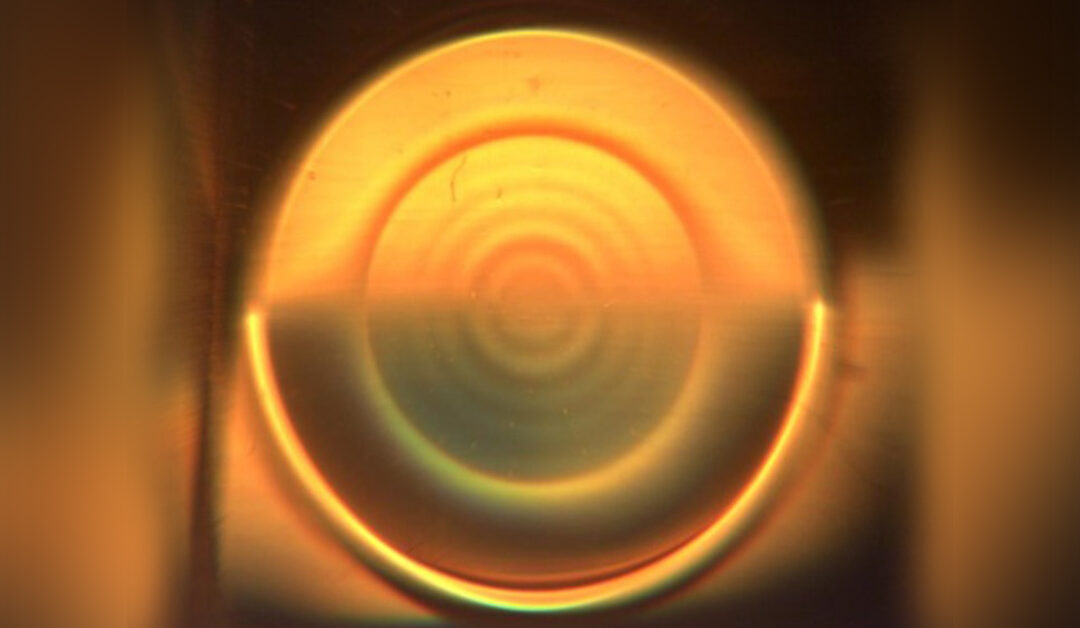

Lentes de contacto con enfoque novedoso

La aplicación de la tecnología de profundidad de foco extendida (EDOF, por su sigla en inglés) a los lentes de contacto ha traído un enfoque novedoso a la corrección de la presbicia y de la miopía. Se han desarrollado diseños sofisticados de EDOF que generan una...TIPS MERCADEO PARA LENTES DE CONTACTO